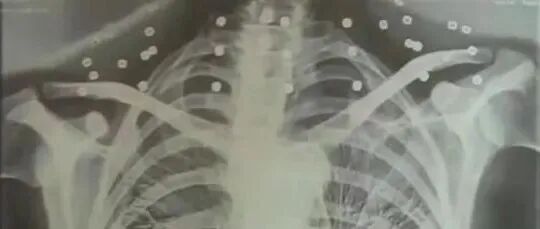

“老先生,您把项链取下来再做CT”“你看是不是弹片”

“老先生您要把项链取下来再做CT”“我从来没戴过项链你看会不会是弹片?”这张照片是今年82岁的吴以先老人拍摄的一张CT照20年前吴以先在一次做CT检查时医生误以为他戴了项链于是提醒要取下来再做检查但实